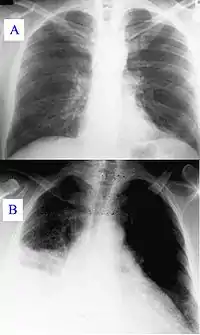

Особливість атипових пневмоній полягає в переважанні симптомів загальної інтоксикації, які посувають на другий план легеневі прояви, звертає на себе увагу відсутність інфільтративних змін на рентгенограмі легенів в перші дні хвороби (так званий інтерстиціальний тип ураження). Перебіг таких пневмоній непередбачуваний: вони можуть перебігати як малосимптомно, так і тяжко, з розвитком небезпечних для життя ускладнень. Труднощі діагностики та різноманітність клінічних проявів часто обумовлюють пізню госпіталізацію хворих до стаціонару, пізню постановку діагнозу та помилки у виборі терапії. Якщо ураження легенів є головним проявом перебігу, то нерідко виділяють так звані «первинні атипові пневмонії (англ. primary atypical pneumonia)» (мікоплазми, легіонели, коронавіруси тощо)[5].